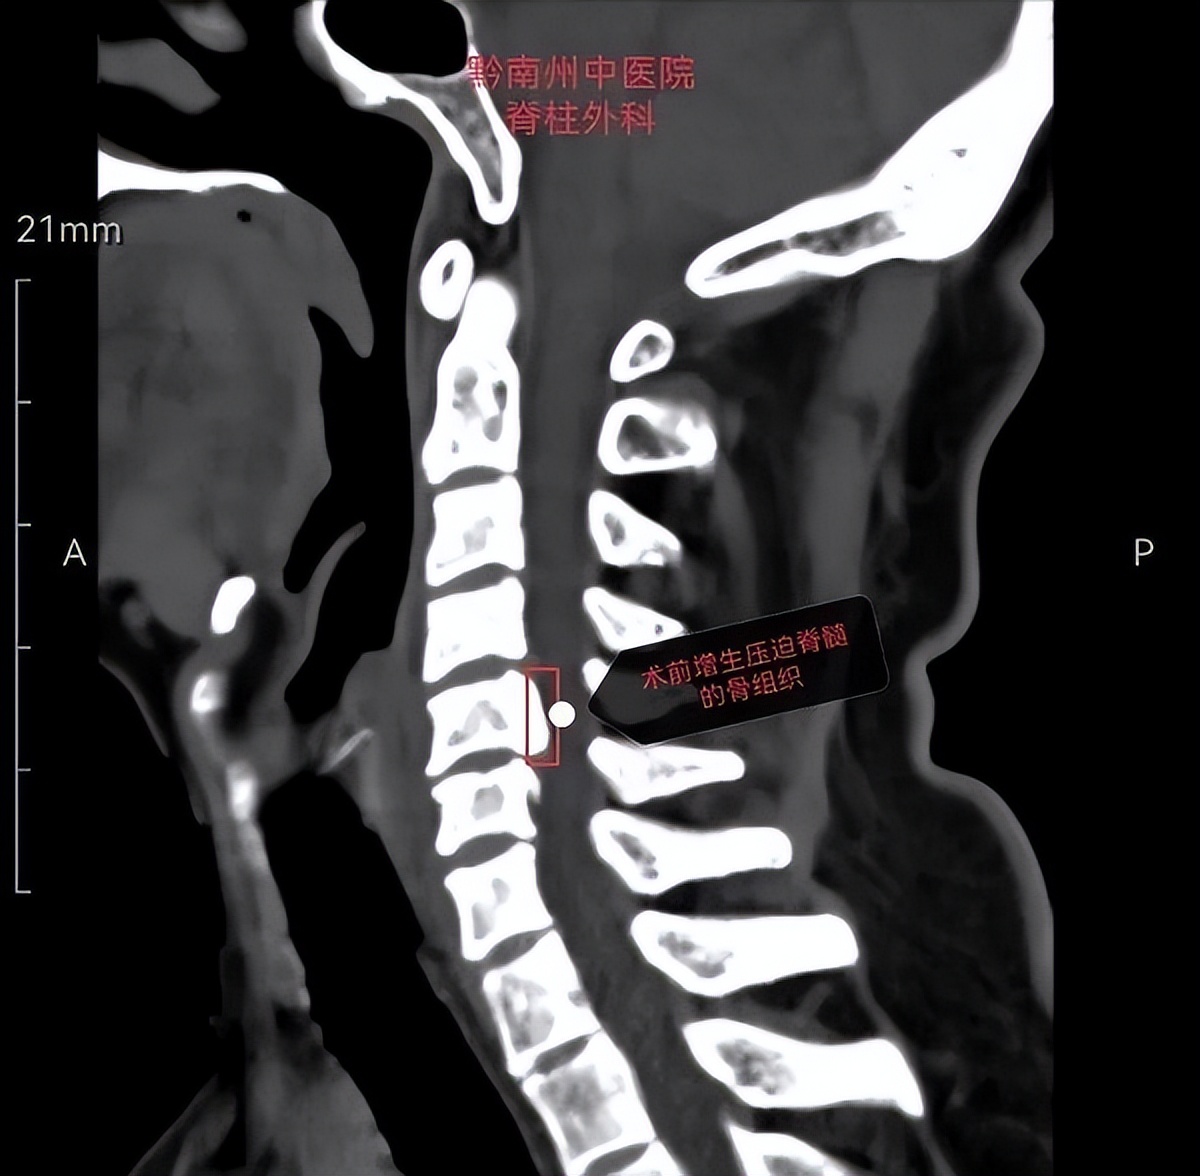

患者男性,49岁,因颈肩部及右上肢放射痛1+月入院。入院后对患者进行了详细的病情问诊、细致的体格检查以及整合患者所有影像学检查,诊断为神经根型颈椎病。同时患者还因为存在颈椎第5节后纵韧带骨化而导致脊髓收到了明显压迫。对患者进行系统保守治疗后,患者仍感到颈肩部及右上肢放痛没有明显缓解,因此向患者告知手术治疗方案。经过和患者及其家属详细交流病情后,患者和家属表示要求通过手术治疗,不仅缓解右肩部和右上肢的疼痛感,同时可以缓解脊髓的压迫,避免出现脊髓损伤而导致瘫痪的风险。

在患者和家属要求手术治疗后,脊柱外科病区主任程刚副主任医师立即组织全科室进行病情讨论,认为根据该病人的病情、影像学检查结果来看,符合目前为止最新改良颈椎前路手术术式之一的“颈前路椎体X型截骨融合术”,并且引导全科对手术实施过程进行了严密的设计。一切准备就绪后,对病人实施了该项手术。